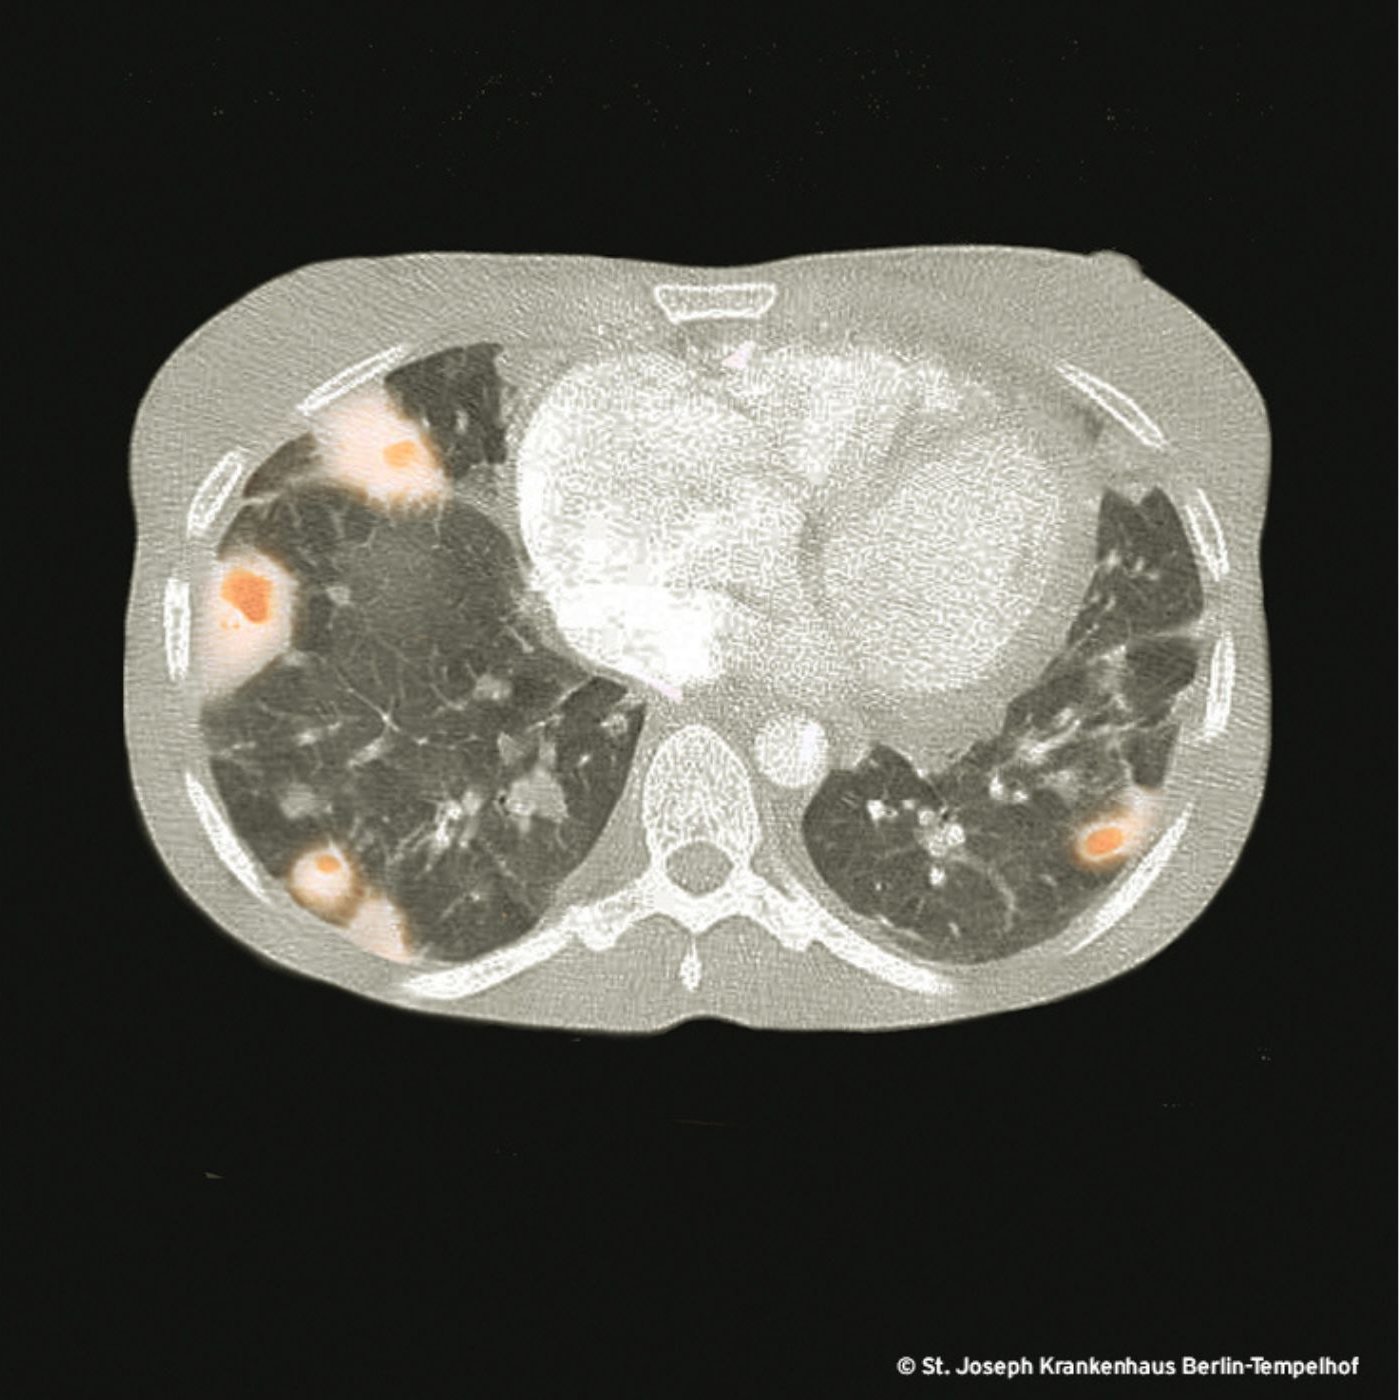

Der Zustand des Herzens unserer Patientin spiegelt sich im Zustand der Lunge wider, und es ist die Bildgebung der Lunge, die bei vielen Patient*innen mit Rechtsherzendokarditis den ersten Hinweis auf die Erkrankung liefert. Im konventionellen Röntgenübersichtsbild ist oft nur ein Teil dieser septischen Streuherde in der Lunge zu sehen. So kommt es, dass die Erkrankung immer wieder als (bilaterale) Pneumonie verkannt und entsprechend behandelt wird. Die Kombination aus bipulmonalen Infiltraten mit einer S. aureus Bakteriämie muss immer eine CT des Thorax triggern: Wenn Sie dann ein solches Computertomogramm sehen, können Sie eine Wette auf eine Rechtsherzendokarditis abschließen und Ihr Kühlschrank wird sich mit Champagnerflaschen füllen.